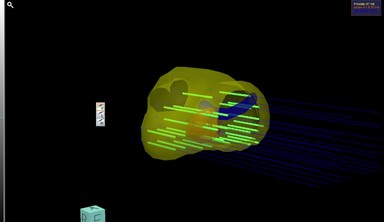

MRIで撮影した高解像度画像とリアルタイムの超音波画像をコンピューター上で融合し、どの位置を採取すればよいかを画面上で確認できる仕組みです。

これにより、狙った病変を正確に採取でき、がんの診断率が向上します。